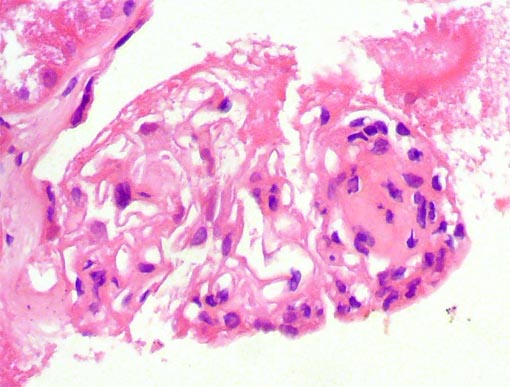

Figura 2.

H&E, X100.